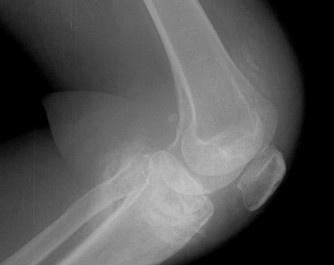

- 常見癥狀:膝關(guān)節(jié)水腫、疼痛、活動受限、跛行、膝關(guān)節(jié)屈伸活動受限、下蹲困難、并伴有疼痛、關(guān)節(jié)周圍局限性壓疼、浮髕試驗陽性

滑膜炎(英文名:synovitis),是一種多發(fā)性疾病,其發(fā)病部位主要在膝關(guān)節(jié)。膝關(guān)節(jié)是人體滑膜最多,關(guān)節(jié)面最大和結(jié)構(gòu)最復(fù)雜的關(guān)節(jié),由于膝關(guān)節(jié)滑膜廣泛并位于肢體表較淺部位,故遭受損傷和感染的機會較多,膝關(guān)節(jié)滑膜炎主要是因膝關(guān)節(jié)扭傷和多種關(guān)節(jié)內(nèi)損傷,而造成的一組綜合癥。容易造成患者暫時或長期部分喪失勞動力,無論對患者和對社會的危害都較大。雖由許多有效的治療方法,但仍有許多患者仍不能治愈。尤其是部分中青年患者,要承擔許多社會和家庭責(zé)任,同時又在長期忍受疼痛的折磨。這無疑是急待醫(yī)務(wù)工作者解決的問題。